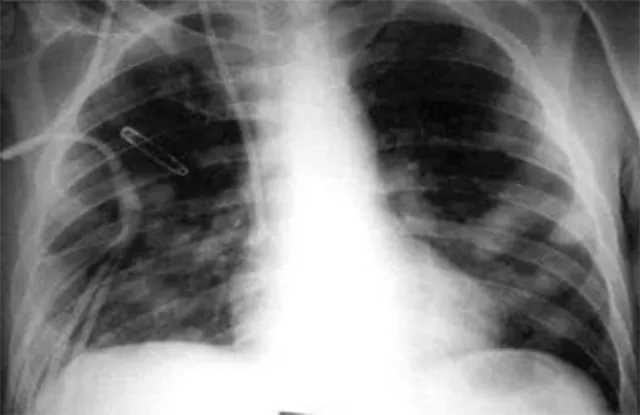

ଭୁବନେଶ୍ବର : ଖୋର୍ଧାରୁ ଚିହ୍ନଟ ହୋଇଛି ‘ଆଲକାଲାଇନ ସଏଲ’ ଫଙ୍ଗସ ସଂକ୍ରମିତ ବିଶ୍ବର ପ୍ରଥମ ବ୍ୟକ୍ତି। ଏମ୍ସ ଭୁବନେଶ୍ବର ଡାକ୍ତରୀ ଦଳଙ୍କ ଚିକିତ୍ସା ପରେ ସେ ବର୍ତ୍ତମାନ ସୁସ୍ଥ ଅଛନ୍ତି। ସମୁଦ୍ର କୂଳରେ ଦେଖାଯାଉଥିବା ଘାସ ହେଲୋଫାଇଟରେ ଏହି ଫଙ୍ଗସ ଦେଖାଯାଏ। ପ୍ରଥମ ଥର ପାଇଁ ଏହି ଫଙ୍ଗସର ଭୟାବହତା ଜଣାପଡ଼ିଛି। ପୀଡ଼ିତ ବ୍ୟକ୍ତି ଛୋଟ ବେଳେ ଫଙ୍ଗସର ସଂସ୍ପର୍ଶରେ ଆସିଥିବା ଅନୁମାନ କରାଯାଉଛି। ମାଇକ୍ରୋ ବାୟୋଲୋଜି ବିଭାଗର ଅତିରିକ୍ତ ପ୍ରଫେସର ବିନୟ ହାଲୁରଙ୍କ ସୂଚନା ଅନୁସାରେ, ଖୋର୍ଧାର ଏହି ୪୦ ବର୍ଷୀୟ ବ୍ୟକ୍ତିଙ୍କ ବେକର ଡାହାଣ ପଟରେ ୧୦ ବର୍ଷରୁ ଉର୍ଧ୍ବ ସମୟ ହେଲା ଫୁଲା ରହିଥିଲା। ଏଥିଯୋଗୁଁ ତାଙ୍କୁ କୌଣସି କଷ୍ଟ ହେଉନଥିଲେ ମଧ୍ୟ ଅନେକ ଡାକ୍ତରଖାନାରେ ଚିକିତ୍ସା କରାଇଛନ୍ତି।

ଯକ୍ଷ୍ମାର ଲକ୍ଷଣ ସହିତ ଏହା ସମାନ ଥିବାରୁ ବିଭିନ୍ନ ସ୍ଥାନରେ ଯକ୍ଷ୍ମା ରୋଗ ଭାବରେ ଚିକିତ୍ସା କରାଯାଉଥିଲା। କିନ୍ତୁ ଯୁବକ ଜଣକ ସୁସ୍ଥ ହେଉନଥିଲେ। କିଛି ଦିନ ପାଇଁ ଫୁଲା ଭଲ ହୋଇ ପୁଣି ୩ରୁ୬ ମାସ ମଧ୍ୟରେ ସେହିଭଳି ଦେଖାଯାଉଥିଲା। ପ୍ରାୟ ଏକ ବର୍ଷ ପୂର୍ବରୁ ଏହି ସମସ୍ୟା ନେଇ ଏମ୍ସ ମେଡିସିନ ବିଭାଗ ଡାକ୍ତର ଅନୁପମ ଦେଙ୍କ ତତ୍ବାବଧାନକୁ ଆସିଥିଲେ। ରୋଗୀଙ୍କୁ ଜ୍ବର ହେଉନଥିଲା କିମ୍ବା ଓଜନ ମଧ୍ୟ ହ୍ରାସ ହେଉନଥିଲା। ତେଣୁ ଅନ୍ୟ କୌଣସି କାରଣରୁ ଏହି ସମସ୍ୟା ସୃଷ୍ଟି ହେଉଥିବା ଆଶଙ୍କା କରି ମାଇକ୍ରୋବାୟୋଲୋଜି ଏବଂ ପାଥୋଲୋଜି ବିଭାଗ ପକ୍ଷରୁ ପୃଥକ ଭାବରେ ତାଙ୍କର ପରୀକ୍ଷଣ କରାଗଲା। ଫଙ୍ଗସ ପ୍ରଭାବରେ ଏଭଳି ହେଉଥିବା ଜଣାପଡ଼ିଥିଲା। ଆବଶ୍ୟକ ଔଷଧ ଦିଆଯିବା ପରେ ୩ ମାସ ମଧ୍ୟରେ ବେକର ଫୁଲା ଉଭେଇ ଯାଇଥିଲା। ପ୍ରାୟ ୯ ମାସ ହେଲା ରୋଗୀ ଜଣକ ଠିକ ଥିବା ଡାକ୍ତର ହାଲୁର କହିଛନ୍ତି। ମେଡିସିନ ବିଭାଗ ଏଚଓଡି ଡାକ୍ତର ଅନୁପମ ଦେ, ମାଇକ୍ରୋବାୟୋଲୋଜି ବିଭାଗ ଡାକ୍ତର ହାଲୁର, ରୁମିତା ଦେ, ପାଥୋଲୋଜି ବିଭାଗ ଡାକ୍ତର ମୁକୁନ୍ଦ ସାବଲେ ପ୍ରମୁଖ ଏହି ଟିମ୍‌ରେ ରହିଛନ୍ତି। ଏଥିପୂର୍ବରୁ ରୁଷିଆରେ ମଧ୍ୟ ଏହି ଫଙ୍ଗସ ଚିହ୍ନଟ ହୋଇଛି।